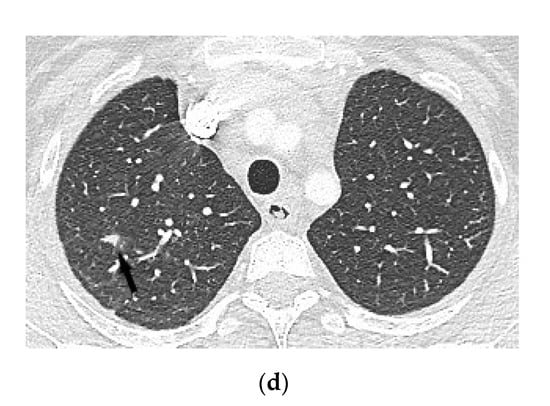

4.1.3. Chest Computed Tomography